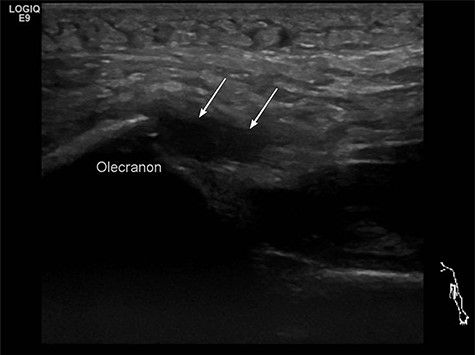

In two patients, an additional MRI to verify the diagnosis was made. In both cases, MRI was ordered by the family doctor before transferring the patients to us. The third patient received an ultrasound sonography, where the rupture could be proofed (Fig. 1).